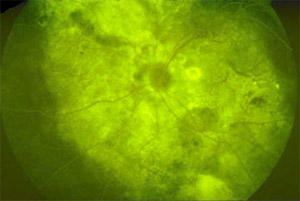

脉络膜梗塞

后极大面积区域显示色素缺失,部分鼻上侧视网膜水肿,多数睫状后动脉梗塞。

注释:进行视网膜动脉充盈,脉络膜显示大面积充盈缺损。

注释:造影照片晚期,脉络膜多数侧副血管充盈